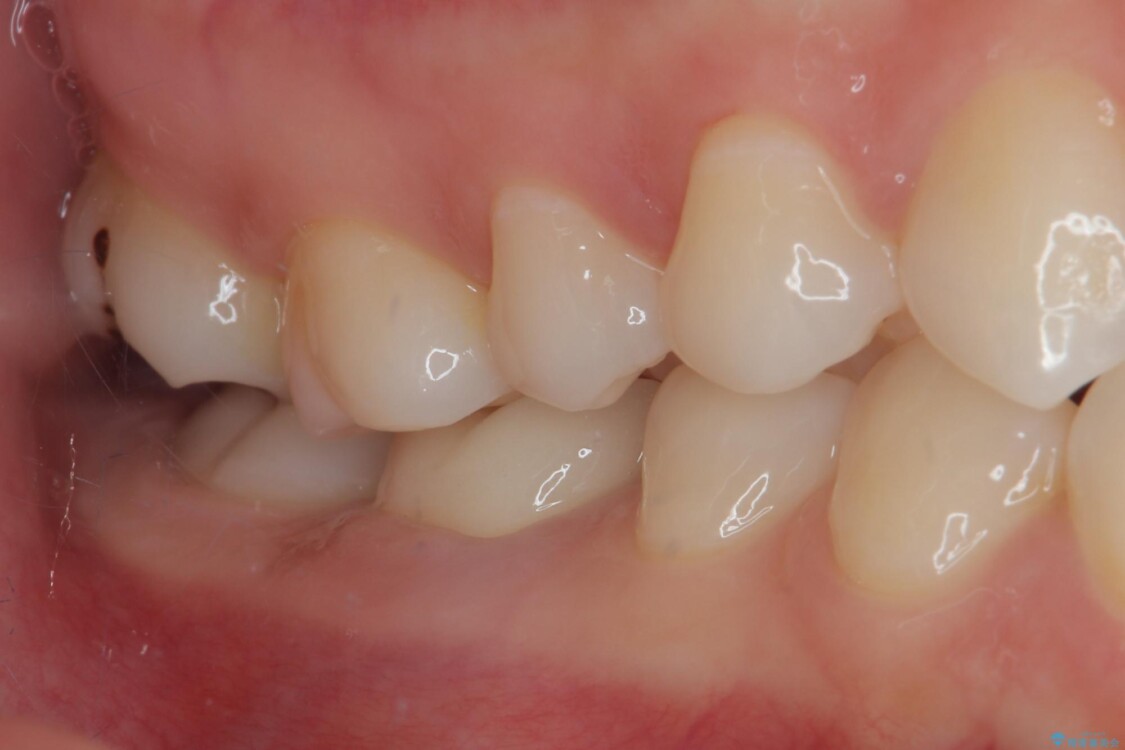

治療後

• ラバーダム使用で再感染リスクを抑えた再根管治療+精密な補綴による長期安定を実現 治療後画像